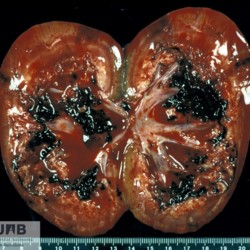

Etiquetes: N-41/00 1 total Canine Specie: Canine Organ: Kidney Lesion: Pyelonephritis Lesion modifier: - Disease: - Files/Expedient: N-41/00 Not viewed Títol Select...Avian (Exotic) (110)Avian (Poultry) (76)Bovine (317)Canine (935)Caprine (47)Equine (257)Feline (326)Ferret (19)General (127)Marine mammal (22)Non-human primate (20)Ovine (328)Porcine (379)Rabbit (61)Reptile (38)Rodent (28)Wildlife (91) Format Select...- (60)Abomasum (37)Adrenal gland (10)Blood (7)Blood vessel (50)Body as a whole (19)Bone (57)Bone marrow (21)Brain (93)Cloaca (1)Diaphragm (2)Ear (5)Esophagus (39)Eye (16)Fetus (12)Gallbladder (23)Gizzard (2)Heart (265)Intestine (356)Joint (32)Kidney (443)Larynx (5)Liver (326)Lung (264)Lymph node (91)Mammary gland (10)Mediastinum (1)Muscle (22)Nasal cavity (22)Nerve (7)Omasum (5)Oral cavity (63)Ovary (14)Oviduct (8)Pancreas (7)Parathyroid (5)Penis (10)Peritoneum (65)Pharynx (9)Pituitary gland (6)Placenta (7)Prostate (8)Proventriculus (3)Reticulum (1)Rumen (28)Sinus (7)Skin (181)Spinal cord (15)Spleen (105)Stomach (125)Teeth (1)Testicle (11)Thoracic cavity (31)Thymus (13)Thyroid gland (5)Tongue (32)Tonsils (11)Trachea (11)Urethra (5)Urinay bladder (61)Uterus (27)Vagina (1)Vulva (1)Yolk sac (1) Cobertura Select...- (152)Abomasitis (26)Abscess (27)Acidosis (1)Adenocarcinoma (20)Adenoma (9)Aerosacculitis (6)Agenesis (1)Agnathia (1)Alopecia (7)Amyloidosis (12)Aneurysm (6)Angiectasis (1)Anthracosis (1)Arteritis (11)Arthritis (15)Arthrogryposis (6)Artifact (4)Ascites (13)Atelectasis (8)Atherosclerosis (5)Atresia (1)Atrial septal defect (2)Atrophy (10)Autolysis (7)Bronchitis (6)Bronchopneumonia (26)Cachexia (2)Carcinoma (103)Cardiomyopathy (19)Cellulitis (2)Chemodectoma (4)Cholangiohepatitis (4)Cholangitis (19)Cholecystitis (4)Cholestasis (5)Chondrodysplasia (2)Chondrosarcoma (2)Chronic passive congestion (13)Chylothorax (2)Cirrhosis (6)Coelomitis (3)Coenurus cerebralis (4)Colitis (40)Congestion (17)Conjunctivitis (5)Coronitis (3)Cryptorchidism (3)Cyst (25)Cystitis (24)Dermatitis (69)Diaphragmatic hernia (4)Dilation (28)Discospondylitis (1)Disseminated intravascular coagulation (7)Dyschondroplasia (1)Dysplasia (29)Ectopia cordis (1)Ectopic ureter (1)Edema (55)Emphysema (5)Encephalitis (5)Endocardiosis (14)Endocarditis (26)Endometritis (5)Enteritis (118)Enterolith (6)Epulis (3)Esophagitis (14)Fasciitis (1)Fibrosis (7)Fibrous osteodystrophy (8)Fistula (1)Folliculitis (3)Fracture (2)Gastritis (34)Gingivitis (5)Glioma (8)Glomerulonephritis (21)Glossitis (25)Glycogenosis (1)Gout (8)Granuloma (2)Granulosa cell tumor (4)Hemangioma (9)Hemangiosarcoma (46)Hematoma (8)Hemoglobinuria (2)Hemopericardium (12)Hemoperitoneum (2)Hemorrhage (100)Hemosiderosis (7)Hemothorax (2)Hepatitis (78)Hernia (11)Histiocytosis (3)Hydatid cyst (11)Hydrocephalus (9)Hydrometra (1)Hydronephrosis (22)Hydropericardium (6)Hydrothorax (3)Hydroureter (5)Hyperkeratosis (8)Hyperostosis (4)Hyperplasia (37)Hypertrophy (9)Hypopigmentation (1)Hypoplasia (7)Hypopyon (1)Impaction (6)Infarction (63)Insulinoma (6)Intussusception (5)Jaundice (17)Laminitis (2)Laryngitis (2)Leiomyoma (5)Leukemia (13)Lipidosis (36)Lipoma (7)Lymphadenitis (45)Lymphadenopathy (7)Lymphangiectasia (6)Lymphangitis (5)Lymphoma (221)Malacia (11)Malignant melanoma (15)Mast cell tumor (11)Mastitis (8)Megaesophagus (2)Melanosis (3)Melena (4)Meningioma (6)Meningitis (6)Meningocele (2)Meningoencephalitis (5)Mesothelioma (5)Methemoglobinemia (2)Mineralization (10)Mucocele (5)Mucometra (1)Multilobular bone tumor (1)Mummification (3)Myelofibrosis (1)Myocarditis (4)Myositis (5)Necrosis (81)Nephritis (113)Nephroblastoma (6)Nephrosclerosis (1)Nephrosis (14)Neuritis (1)Obstruction (13)Omasitis (4)Omphalitis (1)Omphalophlebitis (7)Orchitis (4)Osteoarthrosis (5)Osteomyelitis (9)Otitis (2)Palatoschisis (3)Pancreatitis (3)Panniculitis (3)Papilloma (7)Parakeratosis (14)Patent ductus arteriosus (6)Peliosis hepatis (1)Perforation (17)Pericarditis (35)Peritonitis (39)Persistent right aortic arch (1)Pharyngitis (2)Pheochromocytoma (2)Phlebitis (2)Placentitis (6)Pleuritis (21)Pleuropneumonia (24)Pneumonia (109)Pneumothorax (3)Polycystosis (14)Polyp (5)Polyserositis (6)Posthitis (1)Proctitis (4)Prolapse (3)Prostatitis (3)Proventriculitis (1)Pyelonephritis (24)Pyometra (6)Pyothorax (4)Rhinitis (11)Rumenitis (6)Rupture (24)Salpingitis (3)Sarcoma (57)Sclerosis (1)Scoliosis (2)Seminoma (2)Sequestrum (2)Serous atrophy (14)Sinusitis (7)Splenitis (14)Splenomegaly (9)Spondylitis (6)Spondylosis (1)Stenosis (9)Stomatitis (32)Tenosynovitis (2)Teratoma (3)Thricobezoar (2)Thrombosis (16)Tonsilitis (4)Torsion (13)Tracheitis (4)Tympany (7)Typhlitis (8)Typhlocolitis (4)Ulcer (43)Urethritis (1)Urolithiasis (36)Uroperitoneum (1)Uveitis (1)Vasculitis (15)Ventricular septal defect (3)Volvulus (11) Matèria Select... - (14)- (1653)- (152)Abomasitis - Catarrhal (2)Abomasitis - Catarrhal-hemorrhagic (1)Abomasitis - Chronic (1)Abomasitis - Fibrinous-necrotizing (2)Abomasitis - Hyperplasic (5)Abomasitis - Hyperplasic - Chronic (1)Abomasitis - Necrotic (1)Abomasitis - Necrotizing (2)Abomasitis - Ulcerative (5)Adenocarcinoma (9)Aerosacculitis - Granulomatous (1)Amyloidosis - Chronic (1)Arteritis - Necrotic (2)Arteritis - Necrotizing (1)Arthritis - Chronic (4)Arthritis - Fibrinous-purulent (3)Arthritis - Serous (4)Arthritis - Subacute (1)Ascites - Serous (1)Atrophy - Serous (1)Bronchitis - Catarrhal (3)Bronchitis - Suppurative (1)Bronchopneumonia - Catarrhal-purulent (17)Bronchopneumonia - Fibrinous (1)Bronchopneumonia - Granulomatous (1)Bronchopneumonia - Purulent (1)Bronchopneumonia - Suppurative (5)Carcinoma - Adenocarcinoma (33)Carcinoma - Adenocarcinoma - Hepatocellular (2)Carcinoma - Adenocarcinoma - Mucinous (1)Carcinoma - Basosquamous (1)Carcinoma - Cholangiocellular (3)Carcinoma - Hepatocellular (4)Carcinoma - Metastatic (3)Carcinoma - Squamous cell carcinoma (13)Carcinoma - Transitional cell (2)Cardiomyopathy - Dilated (13)Cardiomyopathy - Hypertrophic (6)Cellulitis - Necrotizing (1)Cholangitis - Chronic (8)Cholangitis - Hyperplasic (3)Cholecystitis - Fibrinous-necrotizing (1)Coelomitis - Fibrinous (1)Coelomitis - Granulomatous (1)Colitis - Catarrhal (3)Colitis - Catarrhal-hemorrhagic (1)Colitis - Fibrinous (1)Colitis - Fibrinous-necrotizing (1)Colitis - Fibrinous-necrotizing (Diphtheritic) (6)Colitis - Granulomatous (2)Colitis - Hemorrhagic (4)Colitis - Hemorrhagic-necrotizing (3)Colitis - Necrotizing (2)Colitis - Ulcerative (6)Congestion - Chronic (2)Conjunctivitis - Hyperplasic (1)Conjunctivitis - Purulent (3)Coronitis - Ulcerative (1)Cystitis - Chronic (3)Cystitis - Fibrinous (1)Cystitis - Fibrinous-necrotizing (1)Cystitis - Follicular (1)Cystitis - Hemorrhagic (6)Cystitis - Hemorrhagic-ulcerative (1)Cystitis - Necrotizing (9)Cystitis - Perforated (1)Dermatitis - Granulomatous (14)Dermatitis - Hyperkeratotic (10)Dermatitis - Hyperplasic (proliferative) (1)Dermatitis - Hyperplastic (10)Dermatitis - Necrotizing (4)Dermatitis - Pustular (4)Dermatitis - Ulcerative (2)Dilation - Chronic (1)Discospondylitis - Necrotizing (1)Dysplasia - Follicular (5)Edema - Interstitial (6)Emphysema - Interstitial (1)Encephalitis - Granulomatous (1)Encephalitis - Nonsuppurative (1)Endocardiosis - Mitral (7)Endocardiosis - Mitral - Chronic (5)Endocarditis - Valvular (6)Endocarditis - Valvular - Mitral (7)Endocarditis - Valvular - Pulmonic (1)Endocarditis - Valvular - Subacute (1)Endocarditis - Valvular - Subaortic (5)Endocarditis - Valvular - Tricuspid (4)Endometritis - Purulent (3)Endometritis - Purulent-hemorrhagic (2)Enteritis - Catarrhal (23)Enteritis - Catarrhal - Acute (1)Enteritis - Catarrhal-hemorrhagic (5)Enteritis - Catarrhal-hemorrhagic - Acute (2)Enteritis - Fibrinous (16)Enteritis - Fibrinous - Acute (3)Enteritis - Fibrinous-necrotizing (7)Enteritis - Granulomatous (14)Enteritis - Granulomatous - Chronic (1)Enteritis - Granulomatous - Multifocal (1)Enteritis - Hemorrhagic (17)Enteritis - Hemorrhagic - Acute (1)Enteritis - Hemorrhagic-necrotizing (1)Enteritis - Hyperplasic (proliferative) (4)Enteritis - Necrotizing (4)Enteritis - Necrotizing - Acute (1)Enteritis - Necrotizing - Hemorrhagic (1)Enteritis - Necrotizing-ulcerative (2)Enteritis - Ulcerative (1)Enteritis - Ulcerative-hemorrhagic (1)Esophagitis - Erosive-ulcerative (6)Esophagitis - Necrotizing (4)Esophagitis - Ulcerative (1)Esophagitis - Ulcerative-necrotizing (1)Fasciitis - Fibrinous-purulent (1)Folliculitis - Purulent (2)Gastritis - Catarrhal (2)Gastritis - Chronic (1)Gastritis - Follicular (1)Gastritis - Hemorrhagic (2)Gastritis - Hemorrhagic-necrotizing (1)Gastritis - Hypertrophic (2)Gastritis - Inclusion bodies (1)Gastritis - Mineralization (1)Gastritis - Mycotic (1)Gastritis - Necrotizing (2)Gastritis - Ulcerative (6)Gastritis - Uremic (3)Gingivitis - Erosive (2)Gingivitis - Hyperplasic (proliferative) (1)Gingivitis - Necrotizing (1)Glomerulonephritis - Chronic (7)Glomerulonephritis - Membranoproliferative (3)Glomerulonephritis - Membranoproliferative - Chronic (1)Glomerulonephritis - Membranous (3)Glomerulonephritis - Membranous - Chronic (1)Glomerulonephritis - Proliferative (2)Glomerulonephritis - Subacute (1)Glossitis - Erosive (2)Glossitis - Granulomatous (6)Glossitis - Hyperplasic (1)Glossitis - Hyperplasic (proliferative) (2)Glossitis - Hyperplastic (1)Glossitis - Necrotizing (2)Glossitis - Necrotizing - Focal (1)Glossitis - Ulcerative (6)Glossitis - Ulcerative - Multifocal (1)Glossitis - Ulcerative - Subacute (1)Glycogenosis (1)Granuloma - Eosinophilic (1)Hemangiosarcoma - Metastatic (2)Hemorrhage - Acute (1)Hemorrhage - Subcapsular (3)Hepatitis - Abscess (9)Hepatitis - Acute (3)Hepatitis - Chronic (4)Hepatitis - Chronic interstitial (6)Hepatitis - Granulomatous (7)Hepatitis - Interstitial - Multifocal (1)Hepatitis - Interstitial - Subacute (1)Hepatitis - Necrotizing (17)Hepatitis - Necrotizing - Acute (2)Hepatitis - Necrotizing - Hemorrhagic (1)Hepatitis - Necrotizing - Subacute (1)Hepatitis - Pyogranulomatous (7)Hepatitis - Subacute (4)Hydronephrosis - Chronic (1)Hydropericardium - Chronic (1)Hyperplasia - Erythroid (1)Hyperplasia - Lymphoid (3)Hyperplasia - Myeloid (1)Hyperplasia - Nodular (8)Hypertrophy - Concentric (2)Hypertrophy - Eccentric (3)Infarction - Acute (17)Infarction - Acute - Multifocal (2)Infarction - Chronic (5)Infarction - Chronic - Multifocal (1)Infarction - Subacute (18)Infarction - Subacute - Focal (2)Laminitis - Chronic (2)Laryngitis - Necrotic (1)Laryngitis - Necrotizing (1)Leukemia - Lymphoid leukemia (2)Leukemia - Non-lymphoid leukemia (6)Lipidosis - Multifocal (1)Lipidosis - Panlobular (1)Lipidosis - Panlobular - Generalized (2)Lymphadenitis - Granulomatous (24)Lymphadenitis - Granulomatous - Chronic (3)Lymphadenitis - Hemorrhagic (1)Lymphadenitis - Necrotizing (5)Lymphadenitis - Necrotizing (caseous) (11)Lymphangitis - Granulomatous (1)Lymphangitis - Purulent (1)Lymphangitis - Ulcerative (1)Lymphoma - Alimentary lymphoma (7)Lymphoma - Cutaneous lymphoma (6)Lymphoma - Lymphosarcoma (2)Lymphoma - Mediastinal lymphoma (1)Lymphoma - Multicentric lymphoma (29)Malignant melanoma - Malignant (1)Malignant melanoma - Metastatic (1)Mast cell tumor - Metastatic (1)Mastitis - Fibrinous-purulent (2)Mastitis - Necrotic (1)Mastitis - Purulent (3)Mastitis - Suppurative (1)Meningitis - Fibrinous-purulent (2)Meningitis - Purulent (4)Meningoencephalitis - Necrotizing (3)Meningoencephalitis - Nonsuppurative (2)Mineralization - Metastatic (4)Myocarditis - Fibrous - Chronic (1)Myocarditis - Granulomatous (1)Myositis - Purulent (2)Necrosis - Acute (1)Necrosis - Cortical (5)Necrosis - Follicular (1)Necrosis - Papillary (8)Necrosis - Papillary - Acute (3)Necrosis - Subacute (3)Necrosis - Tubular (6)Nephritis - Embolic (2)Nephritis - Embolic suppurative (7)Nephritis - Granulomatous (27)Nephritis - Granulomatous - Chronic (1)Nephritis - Granulomatous - Multifocal (1)Nephritis - Interstitial (6)Nephritis - Interstitial - Acute (4)Nephritis - Interstitial - Chronic (41)Nephritis - Interstitial - Subacute (12)Nephritis - Purulent (7)Nephritis - Purulent - Acute (2)Nephritis - Purulent - Multifocal (3)Nephrosis - Cholemic (3)Nephrosis - Hemoglobinuric (10)Omasitis - Fibrinous-necrotizing (1)Omasitis - Hyperkeratotic (1)Omasitis - Necrotizing (2)Omphalophlebitis - Fibrinous-purulent (2)Omphalophlebitis - Purulent (3)Orchitis - Necrotizing (1)Osteomyelitis - Necrotizing (7)Osteomyelitis - Purulent (2)Otitis - Necrotizing (1)Otitis - Proliferative (1)Pancreatitis - Acute (1)Pancreatitis - Chronic (1)Pancreatitis - Granulomatous (1)Panniculitis - Fibrinous-purulent (1)Panniculitis - Necrotic (1)Panniculitis - Parasitic (1)Perforation - Acute (2)Pericarditis - Fibrinous (19)Pericarditis - Fibrinous - Subacute (1)Pericarditis - Fibrinous-necrotizing (1)Pericarditis - Fibrinous-purulent (3)Pericarditis - Fibrous (1)Pericarditis - Fibrous - Chronic (1)Pericarditis - Gangrenous (6)Pericarditis - Granulomatous (1)Pericarditis - Granulomatous - Chronic (2)Peritonitis - Acute (1)Peritonitis - Fibrinous (11)Peritonitis - Fibrinous - Subacute (1)Peritonitis - Fibrinous-purulent (5)Peritonitis - Fibrous (3)Peritonitis - Granulomatous (6)Peritonitis - Purulent (1)Peritonitis - Purulent-hemorrhagic (1)Peritonitis - Pyogranulomatous (3)Pharyngitis - Fibrinous-necrotizing (1)Pharyngitis - Ulcerative (1)Pheochromocytoma - Metastatic (1)Phlebitis - Purulent (1)Placentitis - Fibrinous-necrotizing (1)Placentitis - Necrotic (1)Placentitis - Necrotizing (1)Pleuritis - Chronic (1)Pleuritis - Fibrinous (3)Pleuritis - Fibrinous-purulent (2)Pleuritis - Fibrous (2)Pleuritis - Granulomatous (3)Pleuritis - Hyperplastic (2)Pleuritis - Purulent (2)Pleuritis - Pyogranulomatous (1)Pleuropneumonia - Fibrinous (13)Pleuropneumonia - Fibrinous-necrotizing (5)Pleuropneumonia - Granulomatous (2)Pleuropneumonia - Hemorrhagic-necrotizing (4)Pneumonia - Aspiration (11)Pneumonia - Bronchointerstitial (4)Pneumonia - Bronchointerstitial - Subacute (1)Pneumonia - Embolic (5)Pneumonia - Granulomatous (37)Pneumonia - Granulomatous - Multifocal (4)Pneumonia - Hemorrhagic-necrotizing (2)Pneumonia - Interstitial (7)Pneumonia - Interstitial - Acute (8)Pneumonia - Interstitial - Chronic (6)Pneumonia - Interstitial - Subacute (15)Pneumonia - Necrotizing (2)Pneumonia - Pyogranulomatous (2)Pneumonia - Verminous (5)Polyserositis - Fibrinous (6)Polyserositis - Fibrous (1)Proctitis - Fibrinous-necrotizing (1)Proctitis - Parasitic (2)Prostatitis - Purulent (1)Pyelonephritis - Acute (2)Pyelonephritis - Chronic (3)Rhinitis - Catarrhal (2)Rhinitis - Fibrinous (1)Rhinitis - Granulomatous (4)Rhinitis - Purulent (3)Rumenitis - Acute (1)Rumenitis - Erosive (1)Rumenitis - Necrotizing (1)Rupture - Acute (3)Sarcoma - Fibrosarcoma (12)Sarcoma - Hemangiosarcoma (11)Sarcoma - Histiocytic (7)Sarcoma - Metastatic (1)Sarcoma - Multilobular tumor of bone (1)Sequestrum - Chronic (2)Sinusitis - Suppurative (1)Splenitis - Granulomatous (8)Splenitis - Granulomatous - Chronic (1)Splenitis - Necrotizing (3)Splenitis - Necrotizing (caseous) (2)Spondylitis - Necrotizing (2)Stenosis - Intestinal (1)Stenosis - Valvular - Subaortic (4)Stomatitis - Erosive (12)Stomatitis - Erosive-ulcerative (3)Stomatitis - Fibrinous-necrotizing (1)Stomatitis - Fibrinous-necrotizing (Diphtheritic) (1)Stomatitis - Granulomatous (1)Stomatitis - Hyperplasic (1)Stomatitis - Hyperplasic (proliferative) (1)Stomatitis - Necrotizing (2)Stomatitis - Ulcerative (5)Stomatitis - Ulcerative - Multifocal (1)Stomatitis - Ulcerative-necrotizing (1)Tonsilitis - Necrotizing (4)Torsion - Acute passive hyperemia (5)Tracheitis - Catarrhal (3)Tracheitis - Fibrinous (1)Tracheitis - Granulomatous (1)Typhlitis - Catarrhal (1)Typhlitis - Fibrinous-necrotizing (2)Typhlitis - Hemorrhagic (2)Typhlitis - Ulcerative-hemorrhagic (1)Typhlocolitis - Fibrinous-necrotizing (2)Typhlocolitis - Proliferative (1)Ulcer - Chronic (6)Ulcer - Multifocal (2)Ulcer - Mycotic (1)Ulcer - Perforated (6)Urethritis - Hemorrhagic (1)Urolithiasis - Chronic (2)Uveitis - Granulomatous (1)Vasculitis - Granulomatous (1)Vasculitis - Necrotizing (1) Editor Select...- (1970)Acidosis (2)Actinobacillosis (Pleuropneumonia) (11)Aelurostrongylosis (2)African horse sickness (13)African swine fever (14)Alopecia X (1)Anaplasmosis (4)Anthrax (2)Aortic thromboembolism (feline) (7)Ascariasis (15)Aspergillosis (18)Atopic dermatitis (1)Atrophic rhinitis (3)Babesiosis (6)Blackhead (1)Bluetongue (11)Border disease (2)Bovine viral diarrhea (21)Brucellosis (2)Candidiasis (5)Canine distemper (14)Caprine arthritis-encephalitis (2)Capture myopathy (1)Cardiac insufficiency (17)Caseous lymphadenitis (7)Chlamydiosis (2)Classical swine fever (19)Clostridiosis (19)Coccidiosis (9)Coenurosis (4)Colibacillosis (21)Contagious ecthyma (7)Copper toxicosis (11)Cowdriosis (Heartwater) (3)Cryptococcosis (3)Cryptosporidiosis (2)Cysticercosis (23)Demodicosis (1)Diabetes (1)Dicrocoeliosis (5)Dictyocaulosis (4)Dirofilariasis (7)Discoid lupus erythematosus (3)Echinococcosis (17)Edema disease (7)Egg drop syndrome (1)Encephalitozoonosis (5)Enterotoxemia (1)Enzootic bovine leukosis (46)Epitheliogenesis imperfecta (3)Equine rhinopneumonitis (2)Equine verminous arteritis (strongylosis) (7)Erysipelas (5)Exudative epidermitis (7)Fasciolasis (11)Feline eosinophilic dermatoses (1)Feline hepatic lipidosis (8)Feline histiocytosis (4)Feline infectious peritonitis (38)Feline leukemia (4)Feline lower urinary tract disease (3)Feline panleukopenia (16)Feline viral rhinotracheitis (1)Flea allergy dermatitis (1)Foot and mouth disease (2)Gasterophilosis (4)Glasser's disease (15)Gousiekte (4)Gout (6)Haemonchosis (9)Hemolytic anemia (4)Hemorrhagic diathesis (1)Hepatic insufficiency (11)Hepatosis dietetica (7)Herpesvirosis (6)Hyperadrenocorticism (7)Hyperparathyroidism (10)Hypertrophic osteopathy (6)Hypervitaminosis D (1)Hypodermosis (1)Inclusion body hepatitis (4)Infectious bovine rhinotracheitis (5)Infectious bronchitis (5)Infectious canine hepatitis (13)Influenza (4)Juvenile nephropathy (8)Lamb dysentery (4)Leishmaniasis (28)Leptospirosis (1)Leukosis (5)Listeriosis (4)Lumpy skin disease (3)Maedi-visna (4)Malignant catarrhal fever (12)Mange (6)Mannheimiosis (5)Marek's disease (7)Metabolic bone disease (2)Mucoid enteropathy (5)Mulberry heart disease (5)Myasis (1)Mycobacteriosis (22)Mycosis fungoides (6)Myxomatosis (3)Necrobacillosis (5)Neonatal isoerythrolysis (6)Nocardiosis (4)Oestrosis (2)Onchocerciasis (1)Osteochondrosis (1)Ostertagiosis (6)Ovine pulmonary adenocarcinoma (5)Oxyuriasis (1)Pacheco's disease (4)Papillomatosis (6)Paratuberculosis (18)Parvovirosis (17)Pasteurellosis (11)Pemphigus foliaceus (1)Periodontal disease (1)Polioencephalomalacia of ruminants (4)Polyarteritis nodosa (3)Polycystic kidney disease (13)Porcine circovirosis (11)Porcine dermatitis and nephropathy syndrome (9)Porcine proliferative enteropathy (4)Porcine reproductive and respiratory syndrome (6)Porcine stress syndrome (1)Pox (13)Pregnancy toxemia (3)Proventricular dilatation disease (2)Pseudotuberculosis (yersiniosis) (2)Psittacine beak and feather disease (PBFD) (5)Pyoderma (4)Q fever (4)Rabbit hemorrhagic disease (2)Renal insufficiency (12)Reticuloendotheliosis (2)Rhodococcosis (1)Rickets (1)Rinderpest (2)Salmonellosis (34)Sarcosporidiosis (2)Schmallenberg (7)Septicemia (23)Spirocercosis (11)Streptococcosis (5)Strongylosis (1)Swine dysentery (5)Systemic coronavirosis (5)Tetralogy of Fallot (5)Theileriosis (13)Thromboembolism (5)Toxoplasmosis (11)Transmissible viral proventriculitis (1)Traumatic reticuloperitonitis (3)Traumatism (16)Tuberculosis (58)Ulcerative lymphangitis (1)Uremic syndrome (20)Viral arthritis (6)White muscle disease (9)Wobbler syndrome (2)Xanthomatosis (1)Zygomycosis (4) Idioma Select...- (1180)Bacterial (501)Degeneration (106)Fungal (46)Hemodynamic (112)Idiopathic (22)Inflammation (58)Malformation (88)Neoplasia (343)Nutritional (41)Parasitic (243)Physical/Chemical (93)Toxic (44)Viral (304) Ítem destacat Wildlife Hare. Cysticercus pisiformis (Taenia pisiformis). Courtesy Dr. Raúl Cuadrado